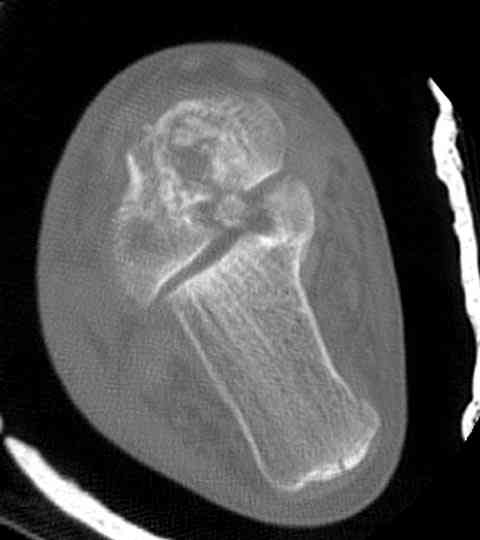

а основании двух видов ренгенограмм невозможно радикально решить о необходимости открытой репозиции или первичного артродеза.

Для оценки состояния нужны дополнительные исследования, например Canale или Broden ренгенограммы и Компьютерная томография.

При переломах тарана всегда имеется риск AVN, а классификация Hawkins поможет разобраться с предполагаемыми осложнениями.

Если в первом типе, когда перелом шейки без смещения, тогда AVN менее 10%, при втором типе когда имеется смещение и вывих тарана в субталарном сочленении меньше 40%, а при типе III когда смещение в голеностопном и субталарном суставах - около 90% и в типе IV, когда происходит полный вывих, риск AVN достигает 100%.

Случай с множественным оскольчатым переломом тарана оперированный из двойного доступа.

На ренгенограмме не уловил многоскольчатость тарана, чтобы доказать, конечно, можно было исследовать на КТ, потом КТ дает ориентацию фрагментов.

Два фрагмента суставной поверхности тарана можно восстановить боковой компрессией шурупами и дополнительно костная пластика.